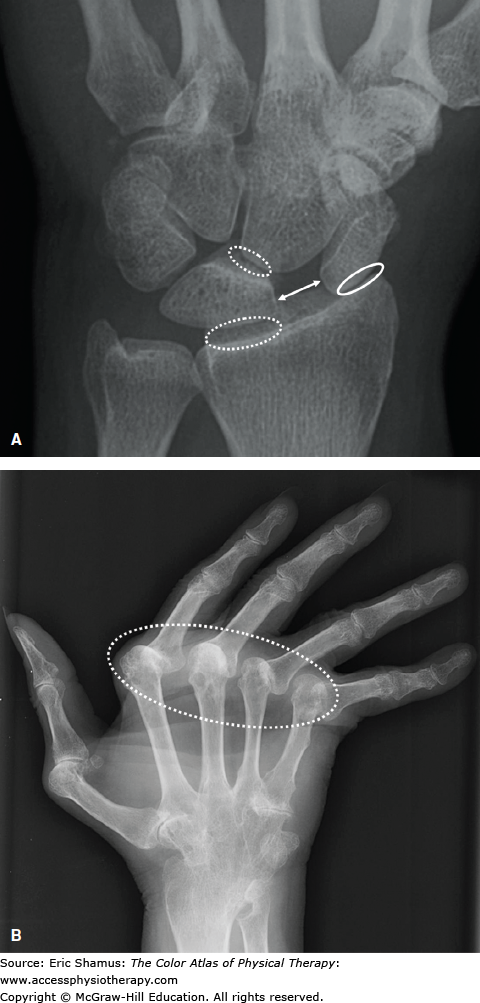

Scenario: A 32-year-old nurse presents to your office with a complaint of intermittent episodes of pain, stiffness, and swelling in both hands and wrists for approximately 1 year. The episodes last for several weeks and then resolve. More recently, she noticed similar symptoms in her knees and ankles. Joint pain and stiffness are making it harder for her to get out of bed in the morning and are interfering with her ability to perform her duties at work. The joint stiffness usually lasts for several hours before improving. She also reports malaise and easy fatiguability for the past few months, but she denies having fever, chills, skin rashes, and weight loss. Physical examination reveals a well-developed woman, with blood pressure 120/70 mm Hg, heart rate 82 bpm, and respiratory rate 14 breaths per minute. Her skin does not reveal any rashes. Head, neck, cardiovascular, chest, and abdominal examinations are normal. There is no hepatosplenomegaly. The joint examination reveals the presence of bilateral swelling, redness, and tenderness of most proximal interphalangeal (PIP) joints, metacarpophalangeal (MCP) joints, the wrists, and the knees. Laboratory studies show a mild anemia with hemoglobin 11.2 g/dL, hematocrit 32.5%, mean corpuscular volume (MCV) 85.7 fL, white blood cell (WBC) count 7.9/mm3 with a normal differential, and platelet count 300,000/mm. The urinalysis is clear with no protein and no red blood cells (RBCs). The erythrocyte sedimentation rate (ESR) is 75 mm/h, and the kidney and liver function tests are normal.

Answer with rationale: D. Small peripheral joints, morning pain and stiffness of more than an hour, bilateral symmetrical swelling. RA tends to affect smaller peripheral joints such as the fingers, wrists, and ankles whereas OA tends to affect larger, weight bearing joints such as knees, hips, and hands. RA has a specific morning stiffness time of over an hour, whereas OA usually lasts 30 minutes or less. Lastly, RA specifically affects bilaterally and symmetrically, whereas OA is usually unilateral and asymmetrical.